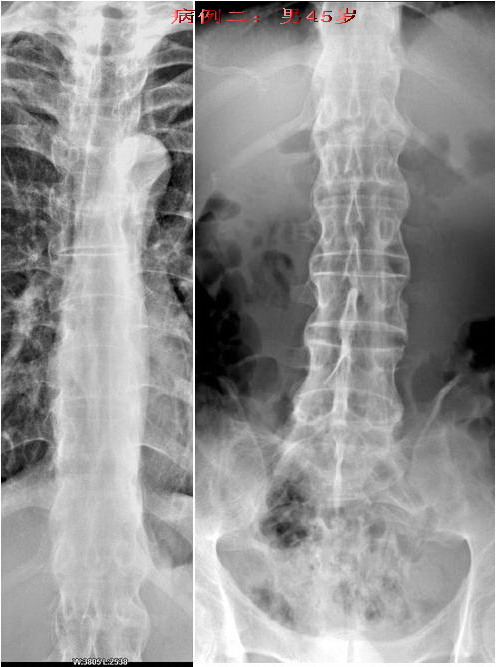

病例二:强直性脊椎炎晚期病例。

男性45岁,患者已有明显的颈部强直症状。从骶髂关节上行至颈椎均呈典型改变(腰椎侧位片已遗失.没有也无所谓)。